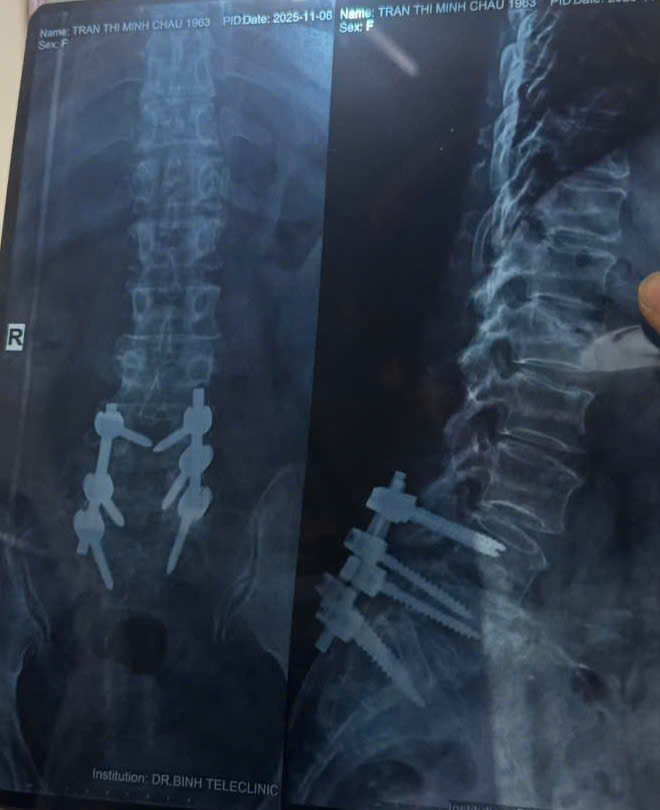

Hình ảnh phim chụp của bệnh nhân vào tháng 11/2025. (Ảnh: BSCC)

Bệnh nhân được tư vấn mổ từ tháng 11/2024. Sau nhiều lần giải thích cặn kẽ, bệnh nhân quyết định phẫu thuật vào ngày 6/1/2025. Kết quả sau mổ khiến chính bệnh nhân thay đổi hoàn toàn suy nghĩ.

Sau phẫu thuật và tập phục hồi chức năng, chỉ vài tuần sau Tết, bệnh nhân đã có thể đi lại, sinh hoạt và đón khách. Đến tháng 3/2025, sức khỏe tổng thể cải thiện rõ rệt. Tháng 11/2025, bệnh nhân tái khám định kỳ, gửi lại phim X-quang cột sống.

“Tròn 1 năm đồng hành, bệnh nhân nói với chúng tôi rằng đi mổ là quyết định sáng suốt nhất trong cuộc đời”, BS Cao Thanh Phong chia sẻ.